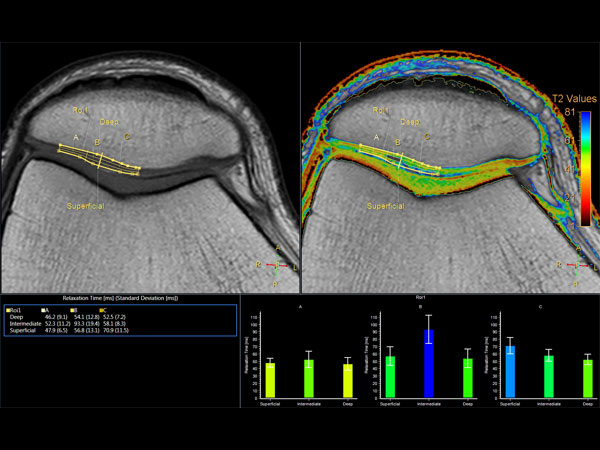

Comprehensive 3D knee imaging with MSK VIEW